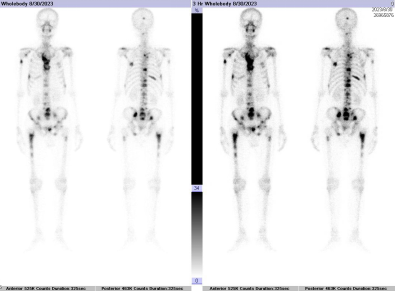

全身骨静态显像正常图像:

全身骨静态显像异常图像(肺癌伴全身多处转移):